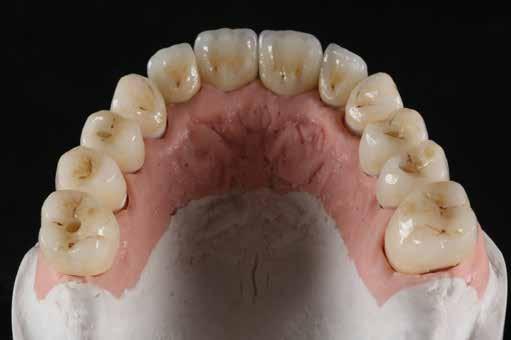

Az előzetes állapotfelmérést és a kezelés megtervezését követően a fogakat minimál invazív módon preparáltuk (1. a-b ábrák), majd az előkészített fogak ínybarázdáiba fonalbehelyező eszköz segítségével (113 Serrated Gingival Cord Packer, Hu-Friedy, Chicago, Illinois) teflonszalagot helyeztünk (Loctite Thread Seal Tape, Henkel Loctite Corp., Egyesült Államok), (1. c ábra). A hagyományos retrakciós fonalak helyett, a rugalmasságuk miatt előnyösebbnek tartjuk a teflonszalagok használatát. A kofferdámot (Dental Dam, Nic Tone, Bukarest, Románia) az előkészített fogakon kívül, az azoktól disztálisan elhelyezkedő egy-egy fognak megfelelően is perforáltuk.

Mivel a felső fogív első kisőrlőfogtól ellenoldali első kisőrlőfogig terjedő részét terveztük kerámia héjak segítségével ellátni (14-24), ezért az izolálást ugyanezen fogív második kisőrlőfogtól második kisőrlőfogig terjedő részére (15-25) helyeztük fel (2. a ábra). A kofferdám rögzítését a második kisőrlőfogakra helyezett kapcsok segítségével (Rubber Dam Clamps #2, Hu-Friedy, Chicago, Illinois, Egyesült Államok) biztosítottuk (2. b ábra). Ezt követően a gumilepedő fogakat körülvevő szélét kézi fonalbehelyező eszközzel és finom levegőáramlattal az ínybarázdákba forgattuk. A folyamat a következőképpen zajlott: a kézi eszközzel a kofferdámot a fognyaknak megfelelően finoman a szulkusz irányába fordítjuk, majd az eszköz végét a fognyaknak megfelelően vezetjük, miközben a lepedőt a puszterből jövő levegő segítsé-

gével finoman az ínybarázdába fordítjuk (2. c ábra). Azokra a fogakra, amelyekre aktuálisan héjakat akartunk helyezni, ezen felül kiegészítő kapcsokat is helyeztünk (Hygenic Brinker Clamp #B4, Coltene/Whaledent Inc., Cuyahoga Falls, Ohio, Egyesült Államok), (2. d ábra) Ebben a stádiumban érdemes a héjakat még bármilyen ragasztóanyag vagy próbapaszta nélkül a helyükre illeszteni (dry tryin). Erre azért volt szükség, hogy még a tényleges ragasztási folyamat megkezdése előtt ellenőrizni tudjuk a restaurátum és a fog pontos illeszkedését, valamint a széli záródási vonalhoz való akadálytalan hozzáférést (3. a ábra). Ideális esetben a héjak felhelyezését párosával, a középvonaltól disztál felé haladva végezzük. Ennek megfelelően a jobb (1.1) és bal felső nagymetszőfogakra (2.1) kapcsokat helyeztünk, majd a szomszédos fogakat teflonszalag segítségével izoláltuk. Ezt követően az 1.1-es és 2.1-es fogak héjak elhorgonyzására szolgáló felszíneit 32%os foszforsavval (Uni-Etch w/BAC, Bisco Dental, Schaumburg, Illinois, Egyesült Államok) 30 másodpercen keresztül kondicionáltuk. Ez után a felszínek vízzel történő lemosása és óvatosan

leszárítása következett (3. b ábra). A fogfelszínek előkészítésének utolsó lépéseként a primert és az adhezívet (OptiBond FL, Kerr Dental Orange, Kalifornia, Egyesült Államok) a gyártói javaslatnak megfelelően a felszínekre applikáltuk, majd 20 másodpercen keresztül polimerizációs lámpával világítottuk (Valo LED Curing Light, Ultradent Products Inc., South Jordan, Utah). Az 1.1-es és 2.1-es fogakat borító héjak ragasztása során világos színű, fényre kötő ragasztócementet (Variolink Esthetic LC, Ivoclar Vivadent, Schaan, Liechtenstein) alkalmaztunk. A ragasztóanyagot először a héjak belső felszínére vittük fel, majd ezeket az előkészített fogfelszínekre helyeztük (3. c ábra). Az approximális felszíneken megjelenő cementfelesleget egy ecset (Profi Natural Bristle Brush, Renfert, Hilzingen, Németország) és fogselyem (Oral-B Glide Pro-Health Deep Clean Floss, Procter & Gamble, Cincinnati, Ohio, Egyesült Államok) segítségével még a ragasztóanyag megvilágítása előtt eltávolítottuk. A megvilágítás során a különböző fogfelszíneket (labiális, meziális, disztális és incizális) 20-20 másodpercen keresztül világítottuk meg (3. d ábra)